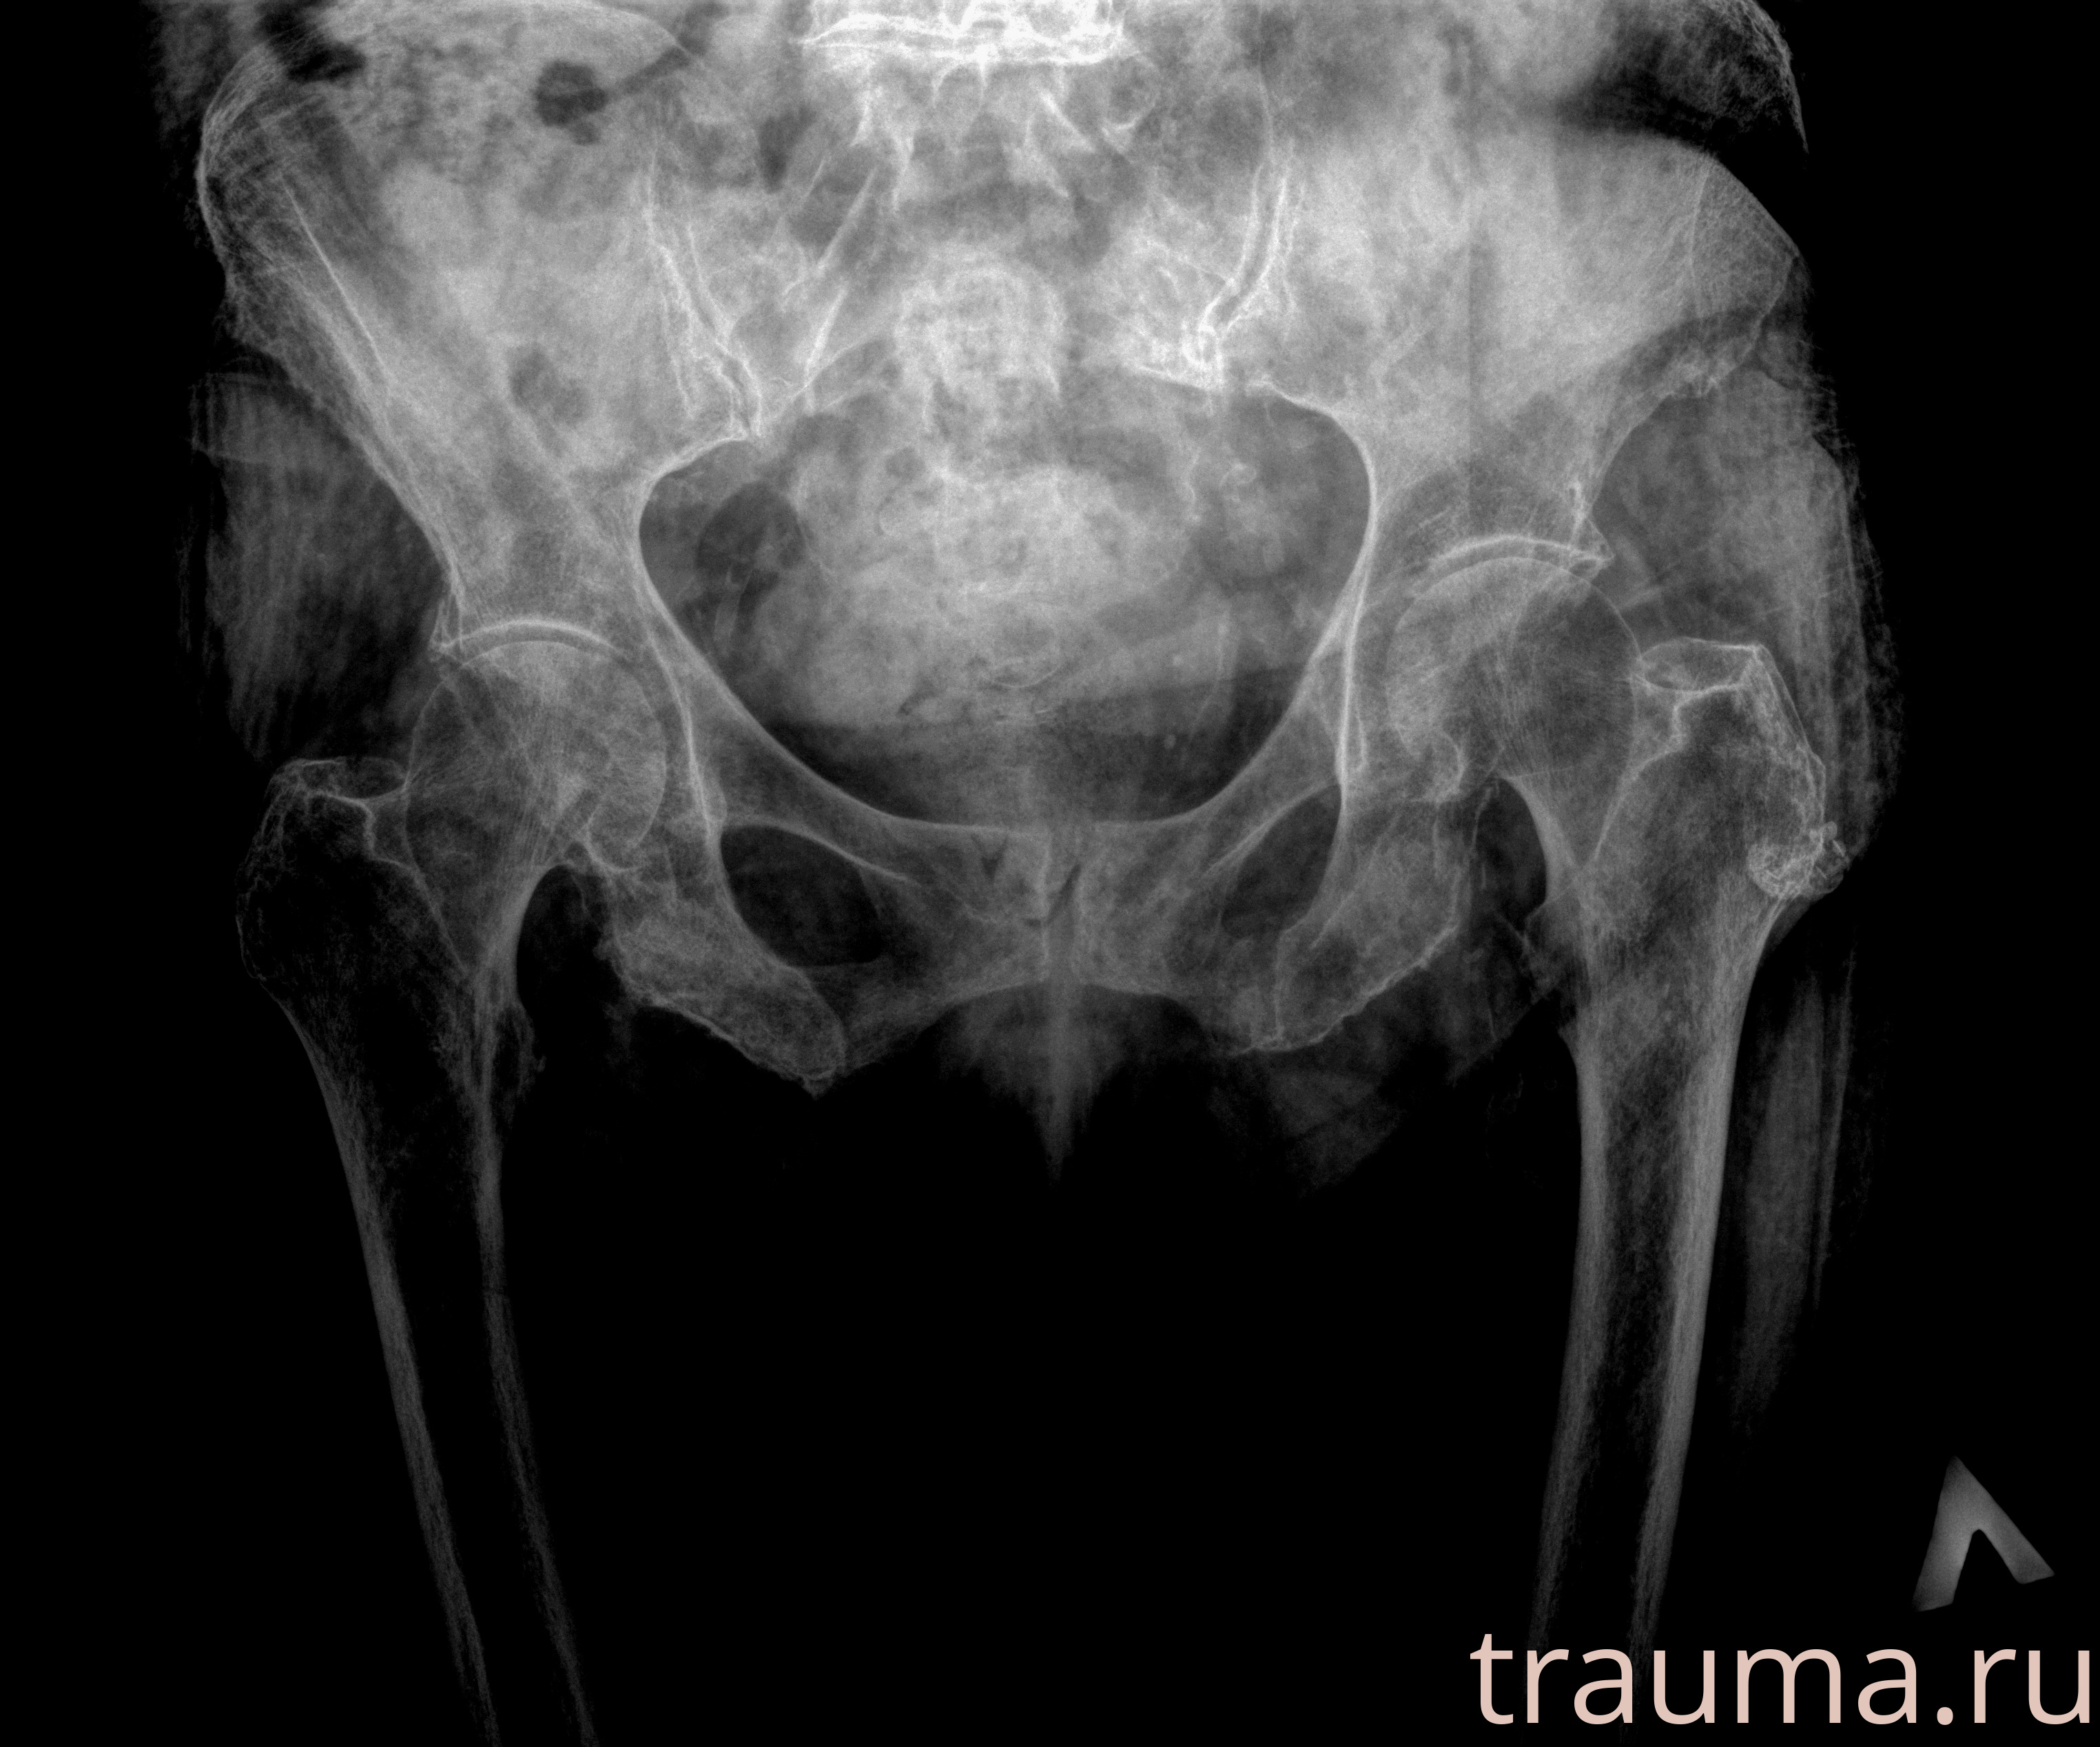

Рентгенограммы

Рентген на дому: по вашему адресу приезжает врач-рентгенолог, травматолог-ортопед с мобильным рентгеновским аппаратом, проводит диагностику травмы или заболевания, делает необходимые рентгенограммы, дает рекомендации по дальнейшему лечению. Получить качественные снимки в домашних условиях возможно благодаря уникальной методике, разработанной МосРентген Центром для института  Склифосовского

при переломе шейки бедра и пневмонии от компании МосРентген Центр - партнера Института имени Склифосовского